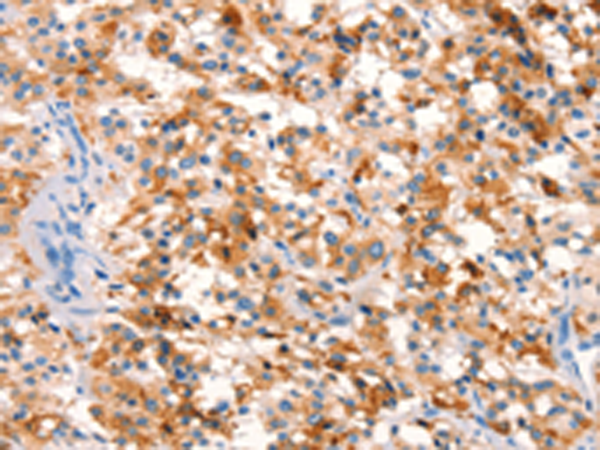

分类: 科研抗体货号: P11099别名: PRP; TSA; PRX2; PTX1; TPX1; NKEFB; PRXII; TDPX1; NKEF-B应用: WB,IHC反应种属: Human, Mouse, Rat